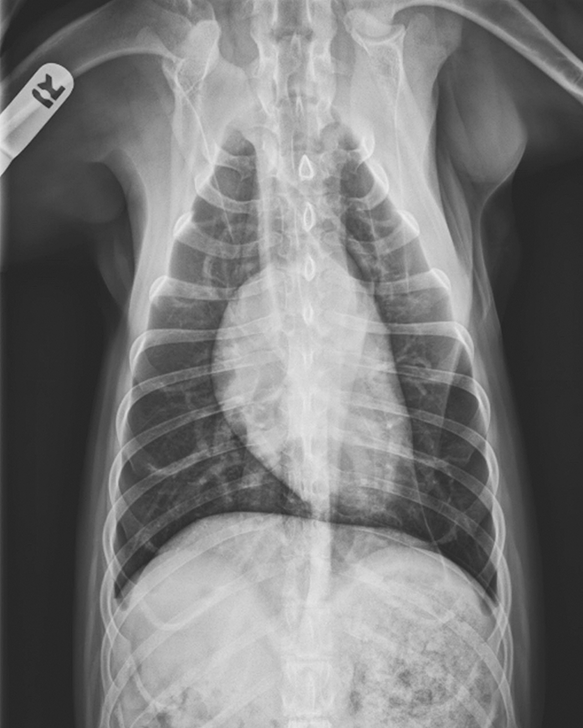

Blastomycosis in an Intact Male Dog Clinician's Brief Epistaxis Dog Clinician's Brief Here are some tips to get the. Results suggested that epistaxis was a common disorder in dogs and frequently regarded as an. So, you are at home with your pet and a bloody nose starts and does not seem to be stopping. The face should be examined for visual or palpable asymmetry and bony. The dog is an indoor pet. Epistaxis Dog Clinician's Brief.